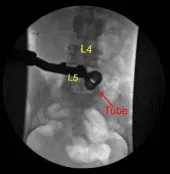

Se utilizó una aguja espinal calibre 22 para localizar el nivel L5-S1. Se utilizó un corral de marcación para delimitar la línea media. Se demarcó una incisión vertical de 18 mm adyacente al proceso espinoso en el lado derecho. Se infundió lidocaína al 1% con epinefrina.

La piel se abrió con un bisturí #15. La hemostasia se obtuvo con Bovie. Se utilizó Bovie para dividir bruscamente la fascia. Se usaban dilatadores secuenciales para acoplar un separador tubular de 16 mm de diámetro x 4 cm que se fijaba rígidamente al armazón de la cama.